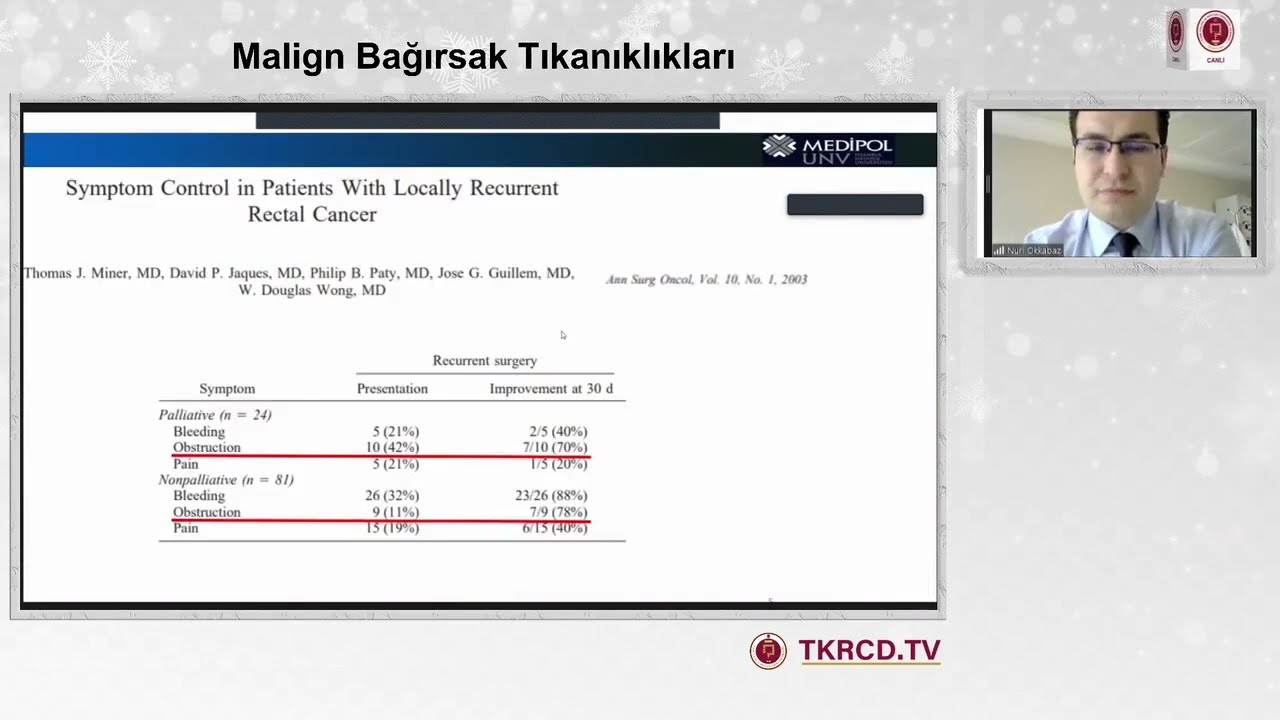

Malignant Intestinal Obstructions

TKRCD Satellite Webinar XVII – March 2021